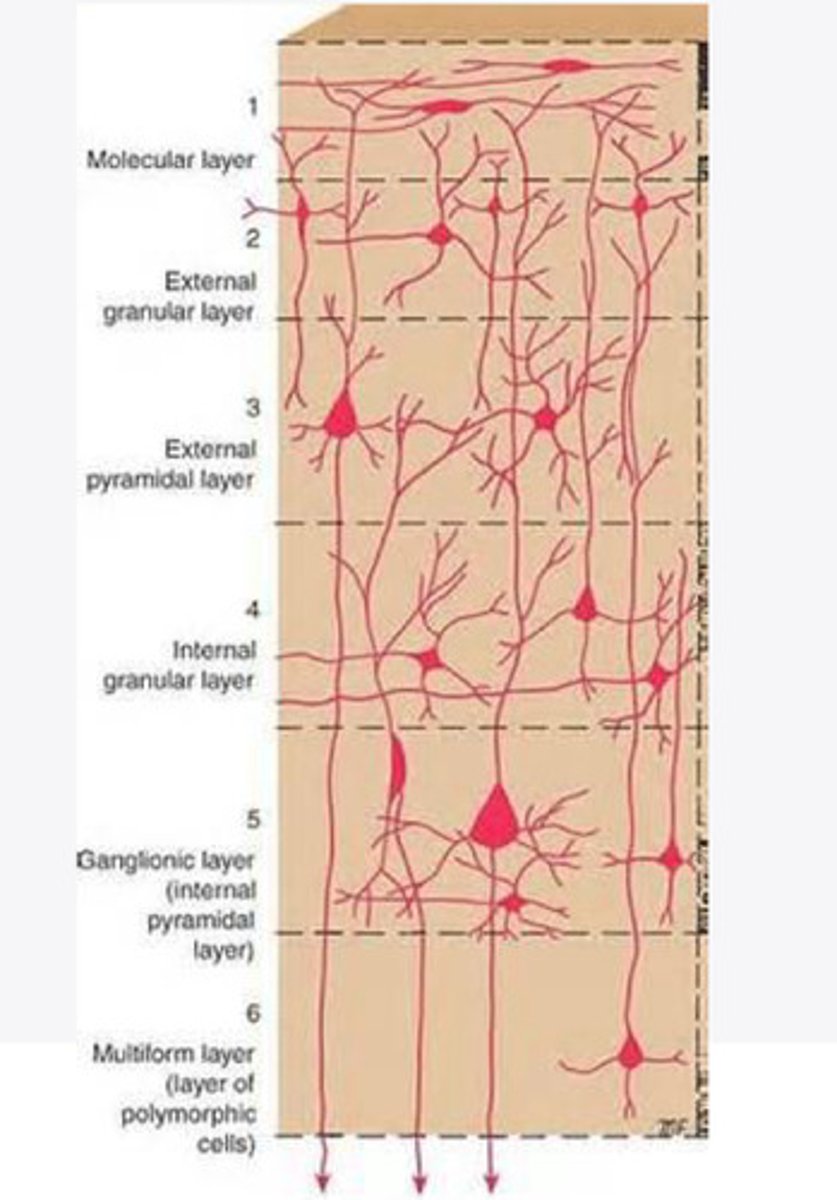

divided into 6 distinct layers, due to varying densities of cell body types within each layer

The cortex of the brain is divided into how many layers? Why is it divided into layers?

Layers of the cortex of the brain pic

2 and 4

What are the layers of the cortex that are associated with input?

3 and 5

What are the layers of the cortex that are associated with output?

molecular layer

What is the name of Layer 1 of the cortex of the brain?

very few cells

Does Layer 1 of the cortex have a lot or few cells?

receives dendrites from internal layers so it may actually function as a coordinating center where layers can communicate action

What does Layer 1 of the cortex do?

1

Every layer sends densities to Layer ____?

1

What layer serves as the "water cooler" of the brain?

external granular layer

What is the name for layer 2 of the cortex of the brain?

receives input from other cortical regions

What is the function of Layer 2 of the Cortex of the brain?

Stellate

What type of cells (stellate/pyramidal) would be most concentrated in Layer 2?

external pyramidal layer

What is the name for layer 3 of the cortex of the brain?

sends output to the other cortical layers

What is the function of Layer 3 of the cortex of the brain?

pyramidal

What type of cells (stellate/pyramidal) would be most concentrated in Layer 3 of the brain?

Layers 2 and 3

What layers are associated with association and commissural fibers?

Layer 3 - axons of cell bodies

Layer 2 - synapse into target areas in Layer 2

What part of the axons is in Layer 2/ in layer 3?

Layer 3 - external pyramidal layer

All axonal cel bodies for association and commissural fibers lie within what layer of the Cortex of the brain?

internal granular

** or called the striate cortex because it is so thick that you can see a line through this layer even in unstrained brain slides

What is the name for the 4th layer of the cortex of the brain?

receives input from the thalamus, geniculocortical layer, and other brainstem areas

What is the function for the 4th layer of the Cortex of the brain?

very thick within the vision, auditory, and somatosensory areas

Is Layer 4 thick or thin within SENSORY areas of the cortex?

Internal pyramidal

What is the name for Layer 5 of the cortex of the brain?

sends axons to the brainstem (corticobulbar) and spinal cord (corticospinal)

What is the function of Layer 5 of the cortex of the brain?

in motor areas of the cortex?

Where is layer 5 very thick in the brain?

the frontal lobe -- very motor heavy

What lobe of the brain will have a thick layer 5 of the cortex of the brain?

the multiform layer

What is the name of layer 6 of the cortex of the brain?

-sends axons back to the thalamus through corticogeniculate fibers

-modulates what information the thalamus sends to the cortex to control the strength of the signal received and modulate what you pay attention to

What is the function of layer 6 of the cortex of the brain?

no

Is layer 6 a motor layer?